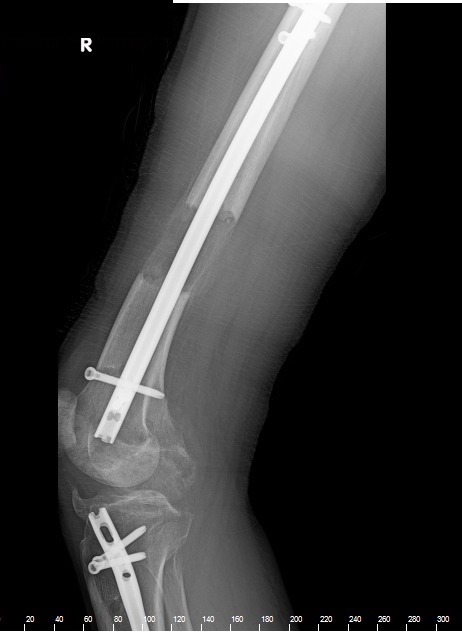

LL on tibias and femurs, both via LON method, 5.5 cm on the tibias and 6 cm on the femurs. I could have gained more, but this puts me at 6’1” with a wingspan/height ratio of ~1 and a legs/torso ratio ~1 SD above mean, which is about ideal. My proportions look completely normal now.

Yeah, most people think I'm about 25. I live like a monk, but I guess it's worth it. And I did the LL in Turkey. Altogether it was about 45k. The healing process is slow, but I can now walk completely normally and even run. The screws and nails hurt though, but I'll be getting them removed.

Oh, and I would add that I highly recommend doing an internal method for the femurs. You don't know what pain is until you've done LON on the femurs.

Thank you. :) And I was measured to be 174 cm before my first surgery, and I gained 11.5 cm, which was verified with two different x-rays, one in the US and one in Turkey. I have a pretty large range though due to spinal compression. I just know that when I wake up I'm well over 6'0. In theory I should be 6'1".

Exactly. My tibia/femur ratio is completely normal. And if you already have a wingspan/height ratio of ~1, I think you could get away with one surgery, but two might look strange. Look at most patients who've lengthened 12+ cm and their arms usually look very short. Apart from the misfortune of being short, I was lucky to at least have a 6' wingspan.

And I paid about 45k in total.

11.5 cm in one operation wouldn't look good. I did it in two: 5.5 cm on my tibias and 6 cm on my femurs. My surgeon was Dr Yuksel. And the z-plasty was $3,000, excluding anesthesia and postoperative care.